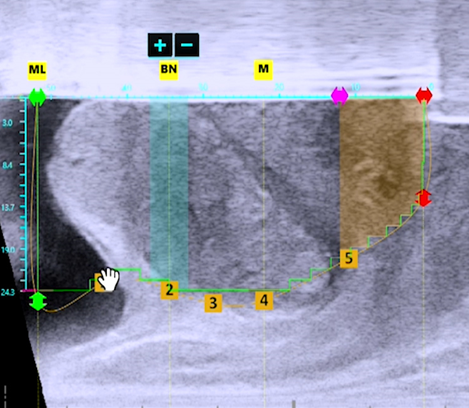

수술 전 막혀있는 전립선 초음파 소견

수술 후 잘 열린 전립선 초음파 소견